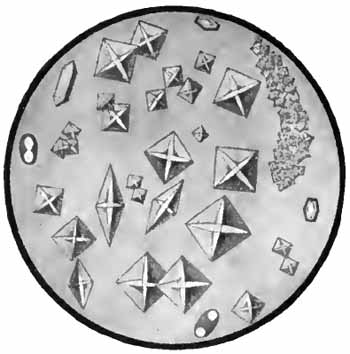

Charcot-Leyden crystals

FIG. 6.—Charcot-Leyden crystals (after Riegel).

[p. 30] 3. Charcot-Leyden Crystals.—Of the crystals which may be found in the sputum, the most interesting are the Charcot-Leyden crystals. They are rarely found except in cases of bronchial asthma, and were at one time thought to be the cause of the disease. They frequently adhere to Curschmann spirals. Their exact nature is unknown.

They are colorless, pointed, often needle-like, octahedral crystals (Fig. 6). Their size varies greatly, the average length being about three or four times the diameter of a red blood-corpuscle.

Other crystals—hematoidin, cholesterin, and, most frequently, fat needles—are common in sputum which has remained in the body for a considerable time.